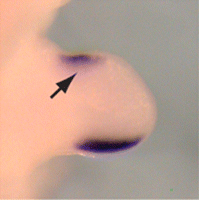

Ulnar or postaxial polydactyly

This is the most common situation, in which the extra digit is on the ulnar side of the hand, thus the side of the little finger. This can also be called postaxial polydactyly. It can manifest itself very subtly, for instance only as a nubbin on the ulnar side of the little finger, or very distinctly, as a fully developed finger. Most commonly, the extra finger is rudimentary, consisting of an end phalanx with a nail, and connected to the hand with a small skin pedicle. Mostly one neurovascular bundle can be identified, with no tendons present in the extra digit. In case of a fully developed extra finger, the duplication usually presents itself at the level of the metacarpophalangeal joint. A triplication of the little finger is very rare. Ulnar polydactyly occurs ten times more often in negroid ethnicities and is most common in African populations.[11] The incidence in Caucasians is reported as 1 in 1,339 live births, compared with 1 in 143 live births in Africans and African Americans. Ulnar polydactyly is also often part of a syndrome.[11] In patients with African ancestry ulnar polydactyly mostly occurs isolated, whereas the presentation in Caucasians is often associated with a syndrome.[8] In almost 14% of all patients, this type of polydactyly is hereditary. It usually passes on in an autosomal dominant manner with variable expression and incomplete penetrance. It is genetically heterogenic, meaning that mutations in different genes can be the cause. When the extra digit is pedicled it can be very movable; however, injuries are rare and have never been reported so far.